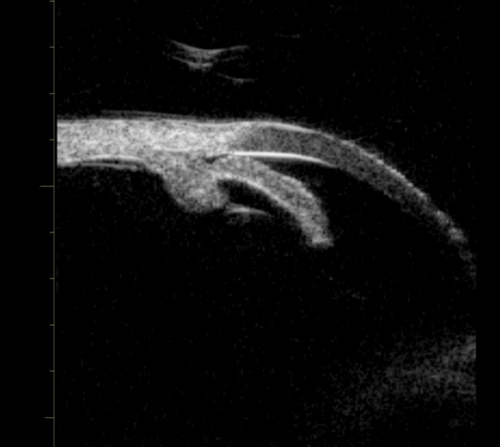

Before PI pupil block causing angle closure.

After PI pupil block resolved; angle open.

Figure 1b (top and above): Pupil block before and after peripheral iridotomy.